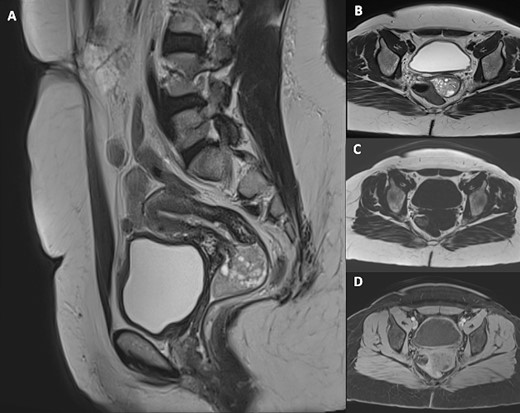

Pelvic magnetic resonance imaging (MRI) revealed a 5 cm × 3 cm × 3 cm intravaginal mass, with endocervical implantation, well-defined, featuring slightly lobulated margins and an oval shape. The mass exhibited the same signal as the endometrium: isointense on T1-weighted images, moderate hypersignal T2 intensity, containing areas of marked hyperintensity on T2. There was no diffusion restriction, and a slight enhancement was observed after Gadolinium injection (Figs 2 and 3). This finding primarily suggested a cervical polyp delivered through the uterine cervix.

Pelvic MRI including sagittal T2-weighted (A), axial T2-weighted (B), axial T1-weighted (C) and axial post-Gadolinium injection (D) images, demonstrating a 5 cm × 3 cm × 3 cm intravaginal mass with endocervical implantation. The mass is well defined, featuring a slightly lobulated oval shape. It exhibits the same signal as the endometrium: isointense on T1-weighted images, moderate hypersignal T2 intensity, containing areas of marked hyperintensity on T2 with slight enhancement after Gadolinium injection.

Pelvic MRI on Diffusion sequence and ADC mapping reveals no diffusion restriction, indicated by an elevated ADC value of (1.5 × 10)–3 mm2/s, suggesting benignity.